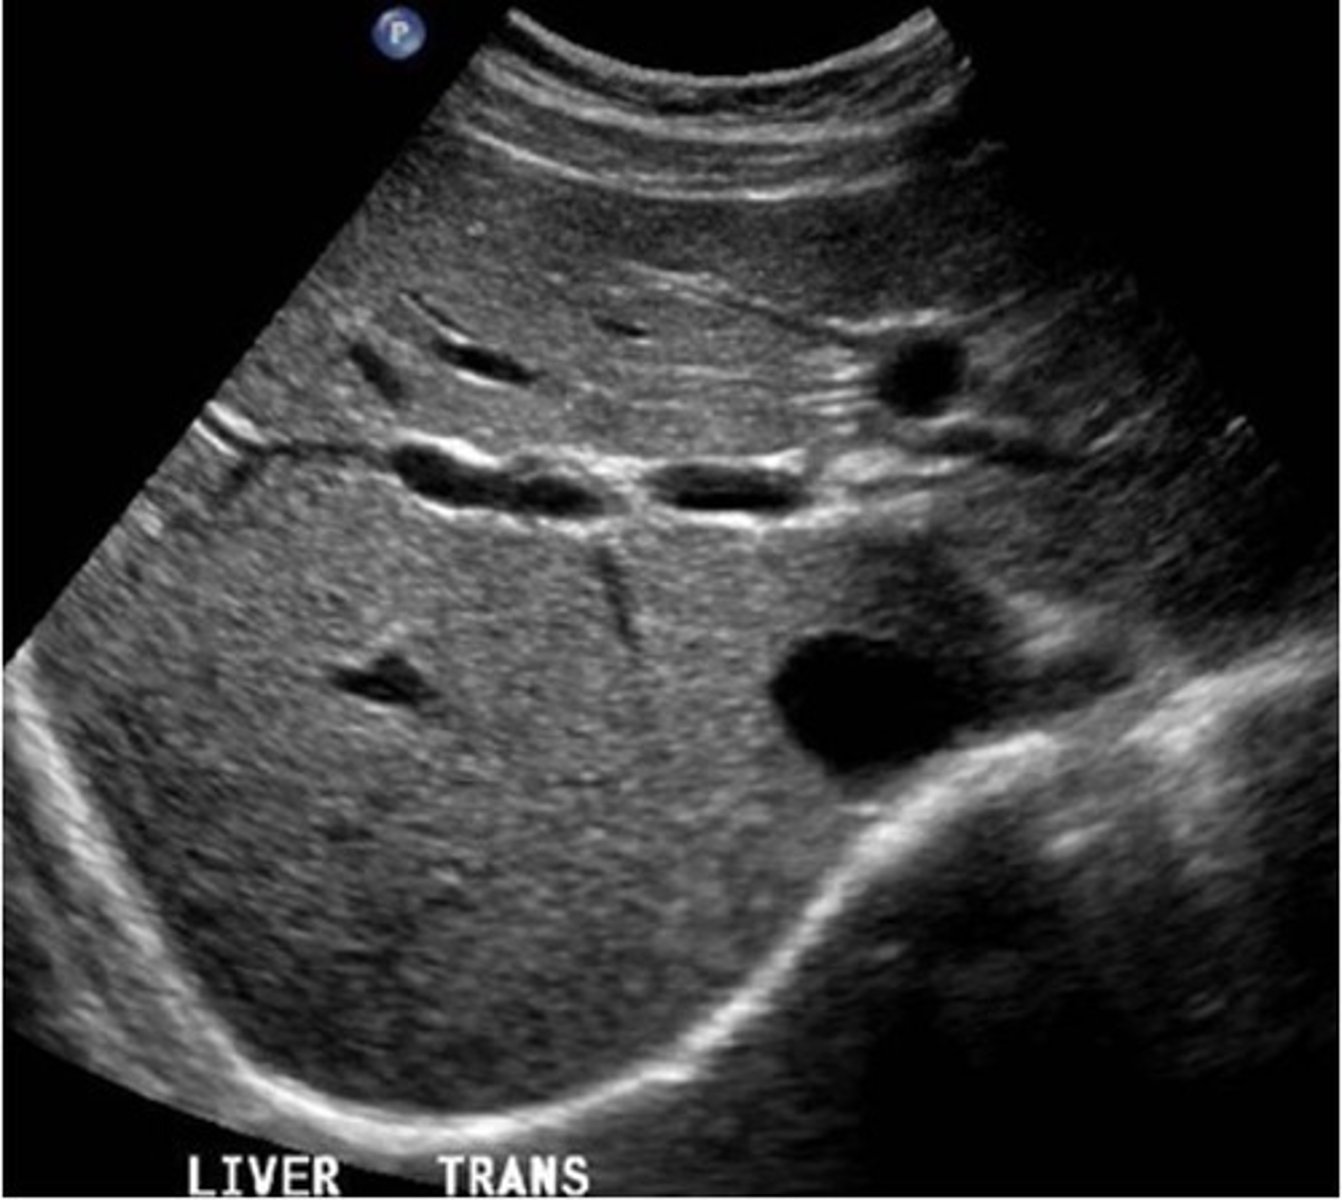

Right lobe of liver and hepatic veins on US

right lobe of liver and kideny on US

Portahepatis and bile duct on US